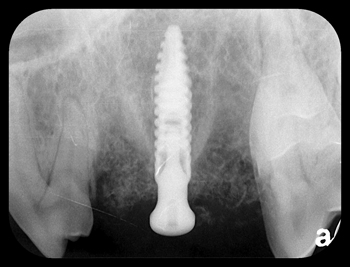

Feline dental implant

Figure 3A: Prior to extraction with flap reflection

Figure 3B: Preop radiograph showing periodontal disease

Pictures shown are cases presented by Rocco Mele, DVM, of Tucson, Arizona, depicting a successful upper fourth premolar extraction, implant placement and bone graft performed on a dog at the same time and a second case of a canine extraction, implant and bone graft at the same time in a cat.